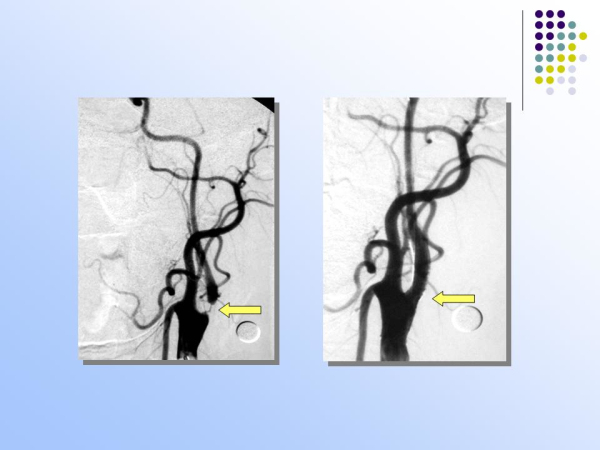

【治疗脑血管病的新技术:血管内介入治疗】—神经内科脑卒中筛查与防治办公室

神经内科

脑卒中筛查与防治办公室